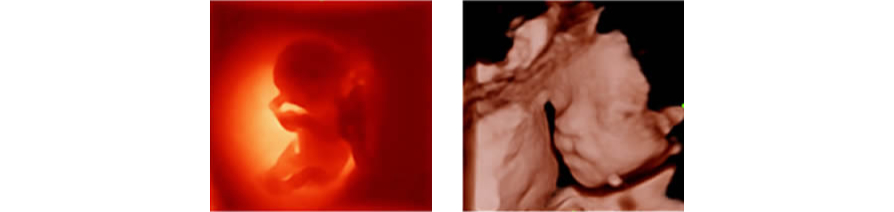

iLive

Ray-casting algoritmas?n? yeni sanal ???kland?rma modalitesi ile entegre eden iLive, insan derisine benzer g?r├╝nt├╝lerle fet├╝s├╝n son derece ger?ek?i bir g?r├╝n├╝m├╝n├╝ olu?turur.

Smart Face

Yeni Z50, tek dokunu?la fetal y├╝z i?in h?zl? ve ak?ll? optimizasyon sa?lar. Hacim verilerinde okl├╝zyonlar? an?nda kald?rabilir, istenmeyen g├╝r├╝lt├╝ bilgilerini ortadan kald?rabilir ve minimum i?lemle fetal y├╝z├╝n optimum g?r├╝n├╝m├╝n├╝ olu?turabilir.